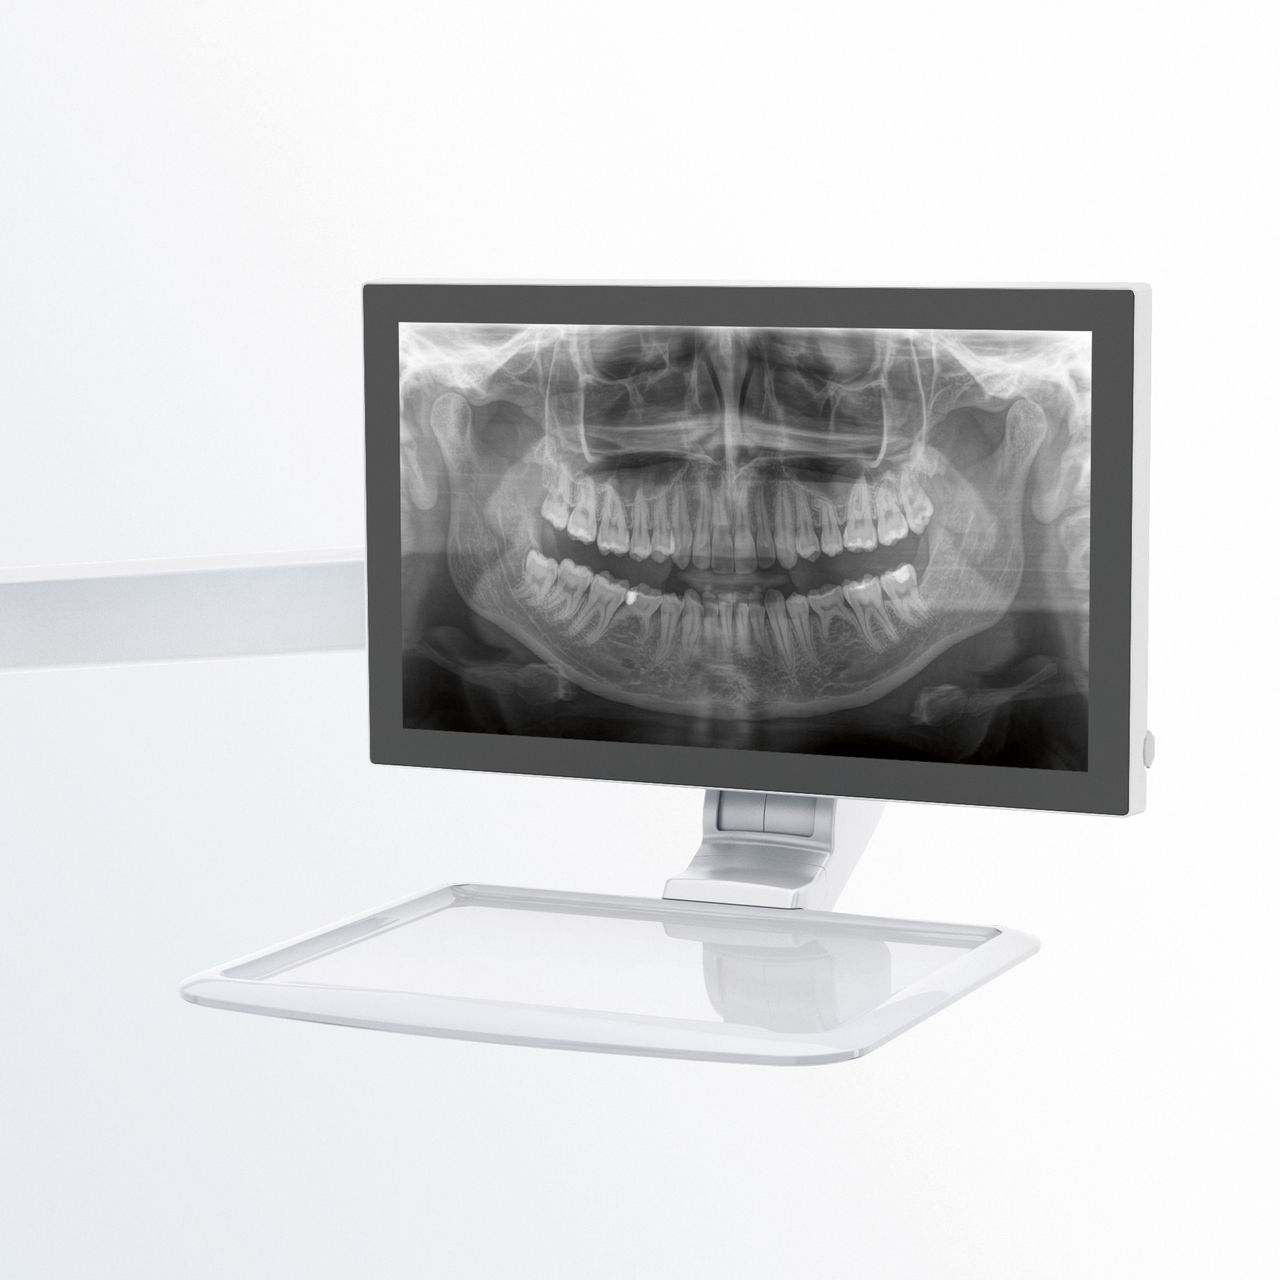

Relaxed and pleasant procedures are equally important for everyone, the patients and the staff alike. It is satisfying and motivating when everything goes according to plan and things go smoothly. The use of Orthophos or Axeos with Sidexis 4 provides you with targeted support. The X-ray systems are simple to use, yet unique in their diagnosis possibilities.. This ensures that every aspect of the treatment process creates a positive experience.